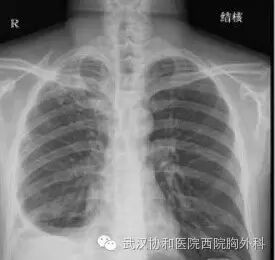

胸痛究竟看哪个科